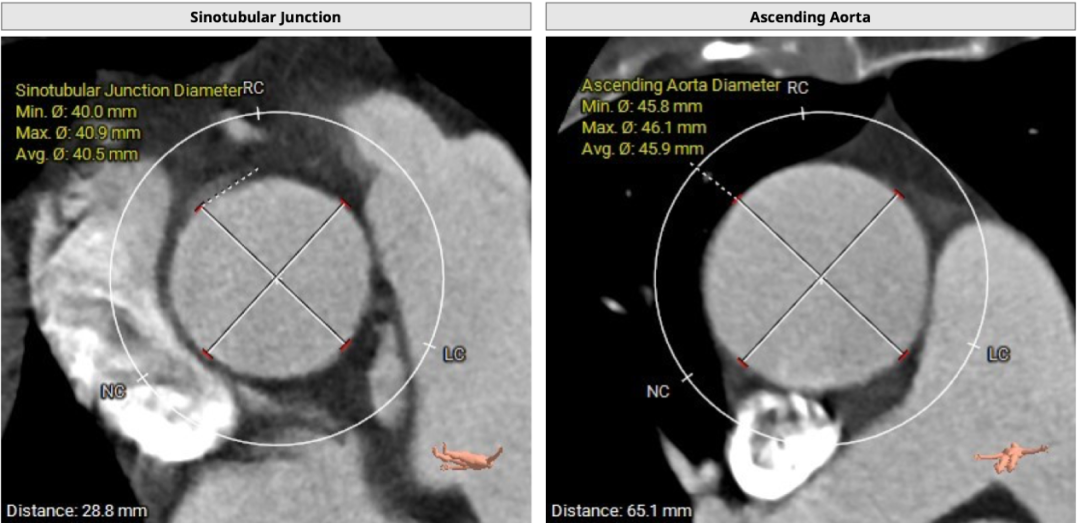

主动脉弓部散在钙化。心室角度60°。